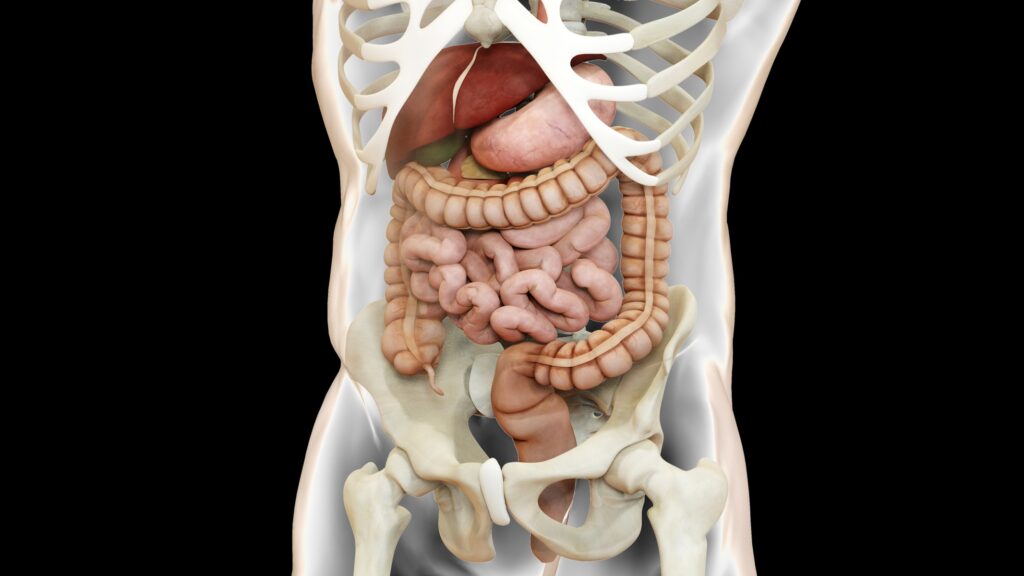

Wyrostek robaczkowy to niewielki narząd będący uwypukleniem jelita grubego, zwykle w okolicy kątnicy – w miejscu, gdzie kończy się jelito cienkiego (dokładniej: jelito kręte) i zaczyna jelito grube. U wielu osób jest traktowany jako narząd szczątkowy, ale współczesna medycyna opisuje też jego potencjalną rolę immunologiczną: zawiera duża ilość tkanki chłonnej i może wspierać lokalną odporność oraz mikrobiotę – stąd czasem mówi się o roli wyrostka robaczkowego jako „rezerwuaru” korzystnych bakterii.

„Ból wyrostka” bywa mylący z nazwy, bo na początku często nie jest „po prawej stronie”. Klasyczny przebieg to ból trzewny, słabo zlokalizowany, startujący w okolicy pępka, a dopiero potem „wędrujący” do prawego dołu biodrowego – zwykle do okolicy prawego dołu biodrowego i nasilenia dolegliwości przy ruchu czy kaszlu. To właśnie ten etap wielu pacjentów opisuje jako prawdziwy „atak wyrostka” i „silny ból brzucha”.

Warto dodać, że nie zawsze objawy są książkowe. Wyrostek robaczkowy znajduje się wprawdzie najczęściej w typowym miejscu, ale jego ułożenie może być zmienne (np. za kątnicą albo w stronę miednicy mniejszej). To wpływa na to, gdzie boli, czy pojawiają się dolegliwości przy oddawaniu moczu, biegunka albo ból bardziej „w miednicy” niż w prawym boku.